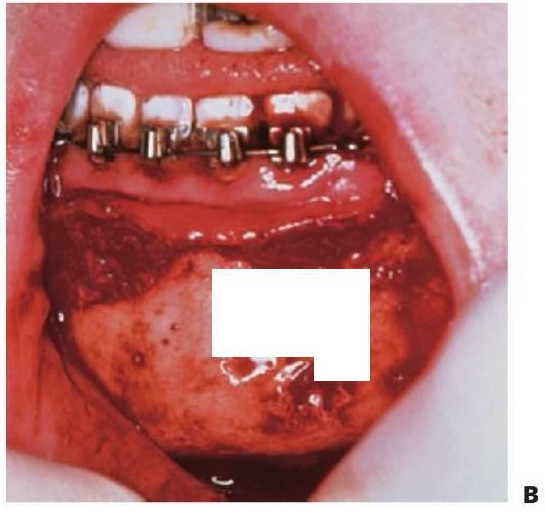

Fractura dentoalveolar

Se produce con más frecuencia en la mandíbula con los dientes anteriores desplazados hada delante con la tabla vestibular. Para mantener el contorno alveolar es conveniente recolocar los dientes con el hueso, lo que se consigue mediante la sutura con nailon grueso (2-0) que se pasa a través de las tablas vestibular y lingual del hueso. Los dientes excesiva mente móviles se deben extraer con cuidado del alveolo conservando la tabla vestibular, que es reposicionada y suturada. (fig. 7.15B).